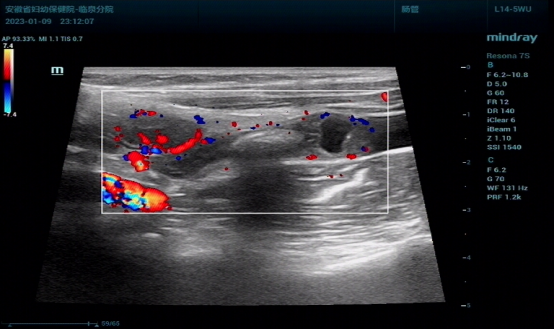

正常的阑尾超声声像图表现为一个细小的管状结构,周围无炎性脂肪包绕,多无多普勒信号。急性阑尾炎直径大于6mm,管壁厚约3mm-5mm,声像图大多为长条形的低回声或是无回声区,形似腊肠,又叫腊肠样回声,腔内见不均的光点,层次模糊,横切面呈“同心圆征”。

(右下腹无回声区,管壁增厚,层次模糊,粘膜层中断,周围炎性浸润的脂肪内血流信号轻度增加)